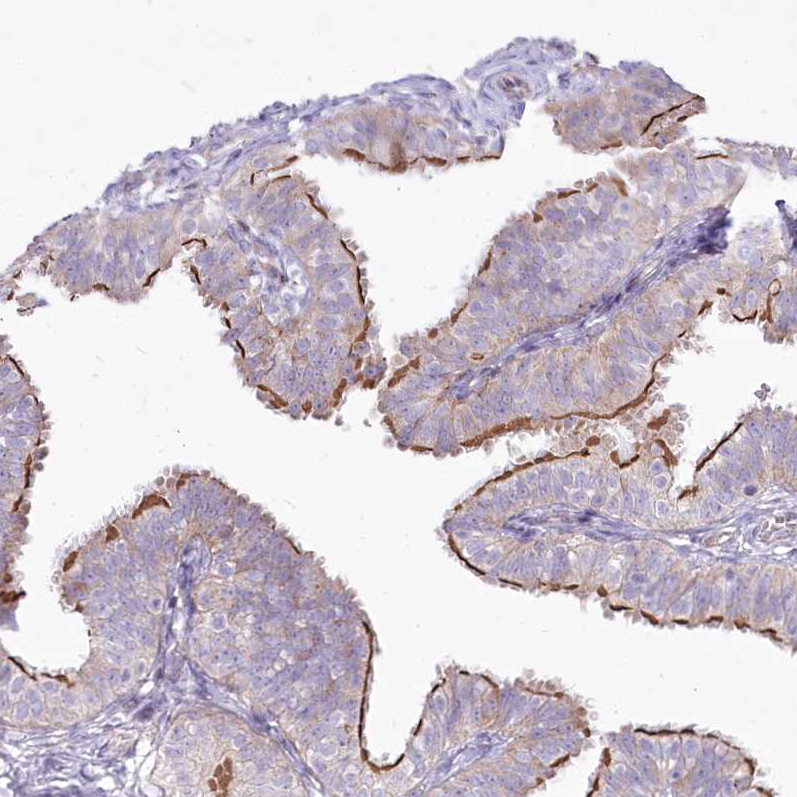

Immunohistochemical staining of human fallopian tube shows strong positivity in cilia in glandular cells.